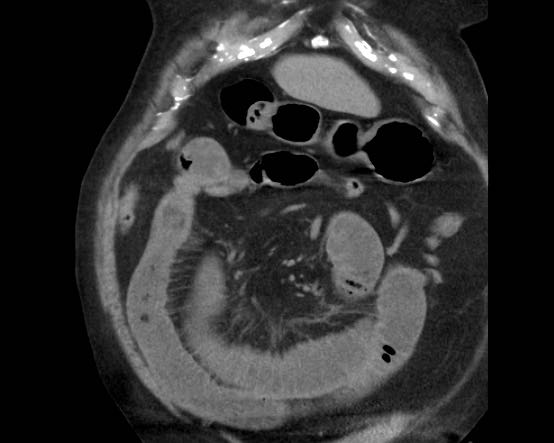

CT trong viêm túi mật cấp

CT có thể rất hữu ích trong các trường hợp siêu âm không cho kết quả chẩn đoán.

Đây là hình ảnh của một bệnh nhân béo phì với đau hạ sườn phải cấp tính trong 6 giờ. CRP 2.

Siêu âm cho thấy túi mật lớn có bùn mật, không quan sát thấy sỏi.

Việc ấn vào túi mật không đáng tin cậy do vị trí cao dưới cung sườn phải.

Không có bất thường siêu âm nào khác.

CT thực hiện cùng ngày cho thấy túi mật lớn với chỉ những thay đổi quanh túi mật kín đáo và không có nguyên nhân nào khác giải thích cho các triệu chứng.

Ngày hôm sau CRP là 105 và CT không tiêm thuốc cản quang lặp lại cho thấy quầng mờ xung quanh túi mật.

Phẫu thuật tiếp theo xác nhận viêm túi mật cấp giai đoạn sớm do sỏi nhỏ trong ống túi mật.